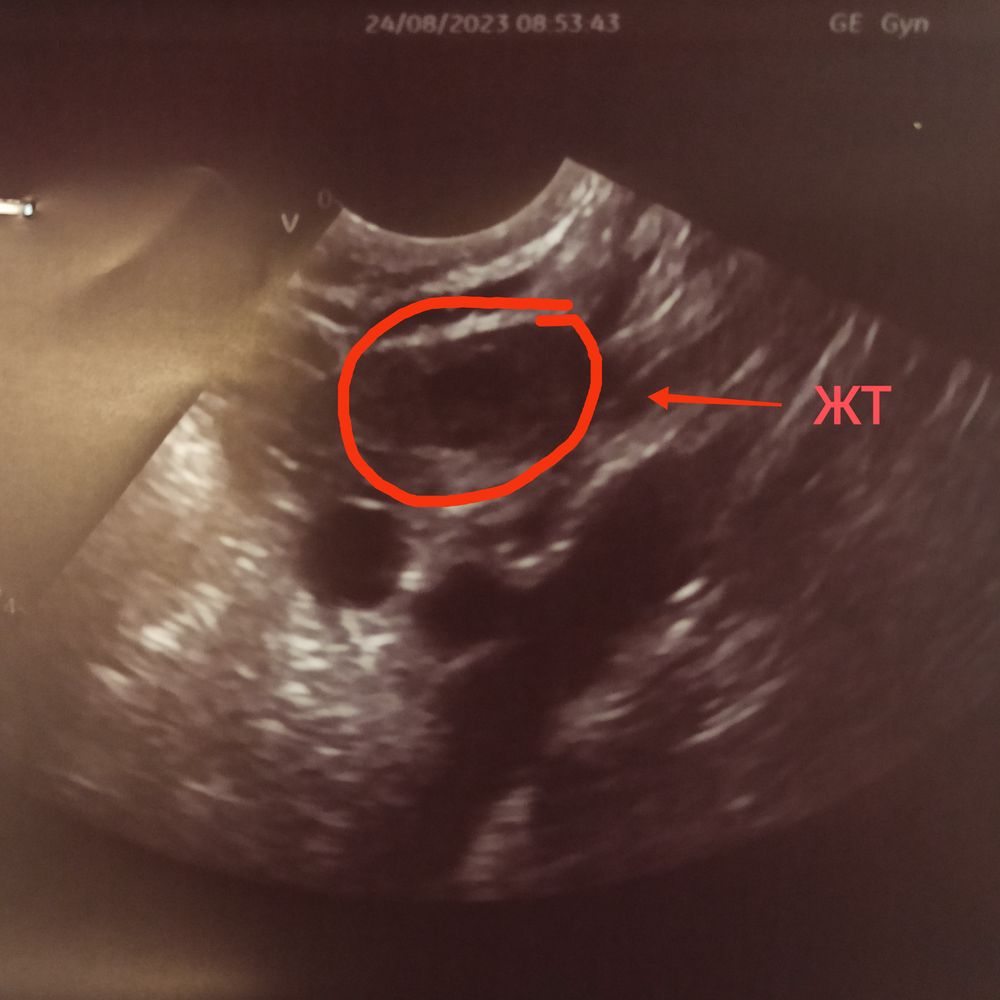

Ксюша в Зачатие 2 года Где желтое тело на узи? Фолликулометрия Делала узи и дали снимок, овуляция была, но не понимаю где желтое тело на снимке. Посмотрите еще 20 записей на эту тему Лучший ответ Алёна Я сама сегодня увидела ЖТ на УЗИ и врач сказал, да это оно Если в заключении нет, значит не увидела 24.08.2023 Ответить Ксюша Алёна, такое большое. Видимо у меня нету( 24.08.2023 Ответить Алёна Планюша , нет наоборот маленькое, 10 мм( 24.08.2023 Ответить Отменить Ответить L А вам зачем такие подробности😁 24.08.2023 Ответить Ксюша Татьяна, в заключении не написано ни слова про желтое тело. Я даже не понимаю есть ли оно вообще … 24.08.2023 Ответить 7 дпо ЖТ... Планирование второй беременности) Чаты Беременных Выберите чат: Январята-2026 Февралята-2026 Мартята-2026 Апрелята-2026 Майчата-2026 Июнята-2026 Июлята-2026 Августята-2026